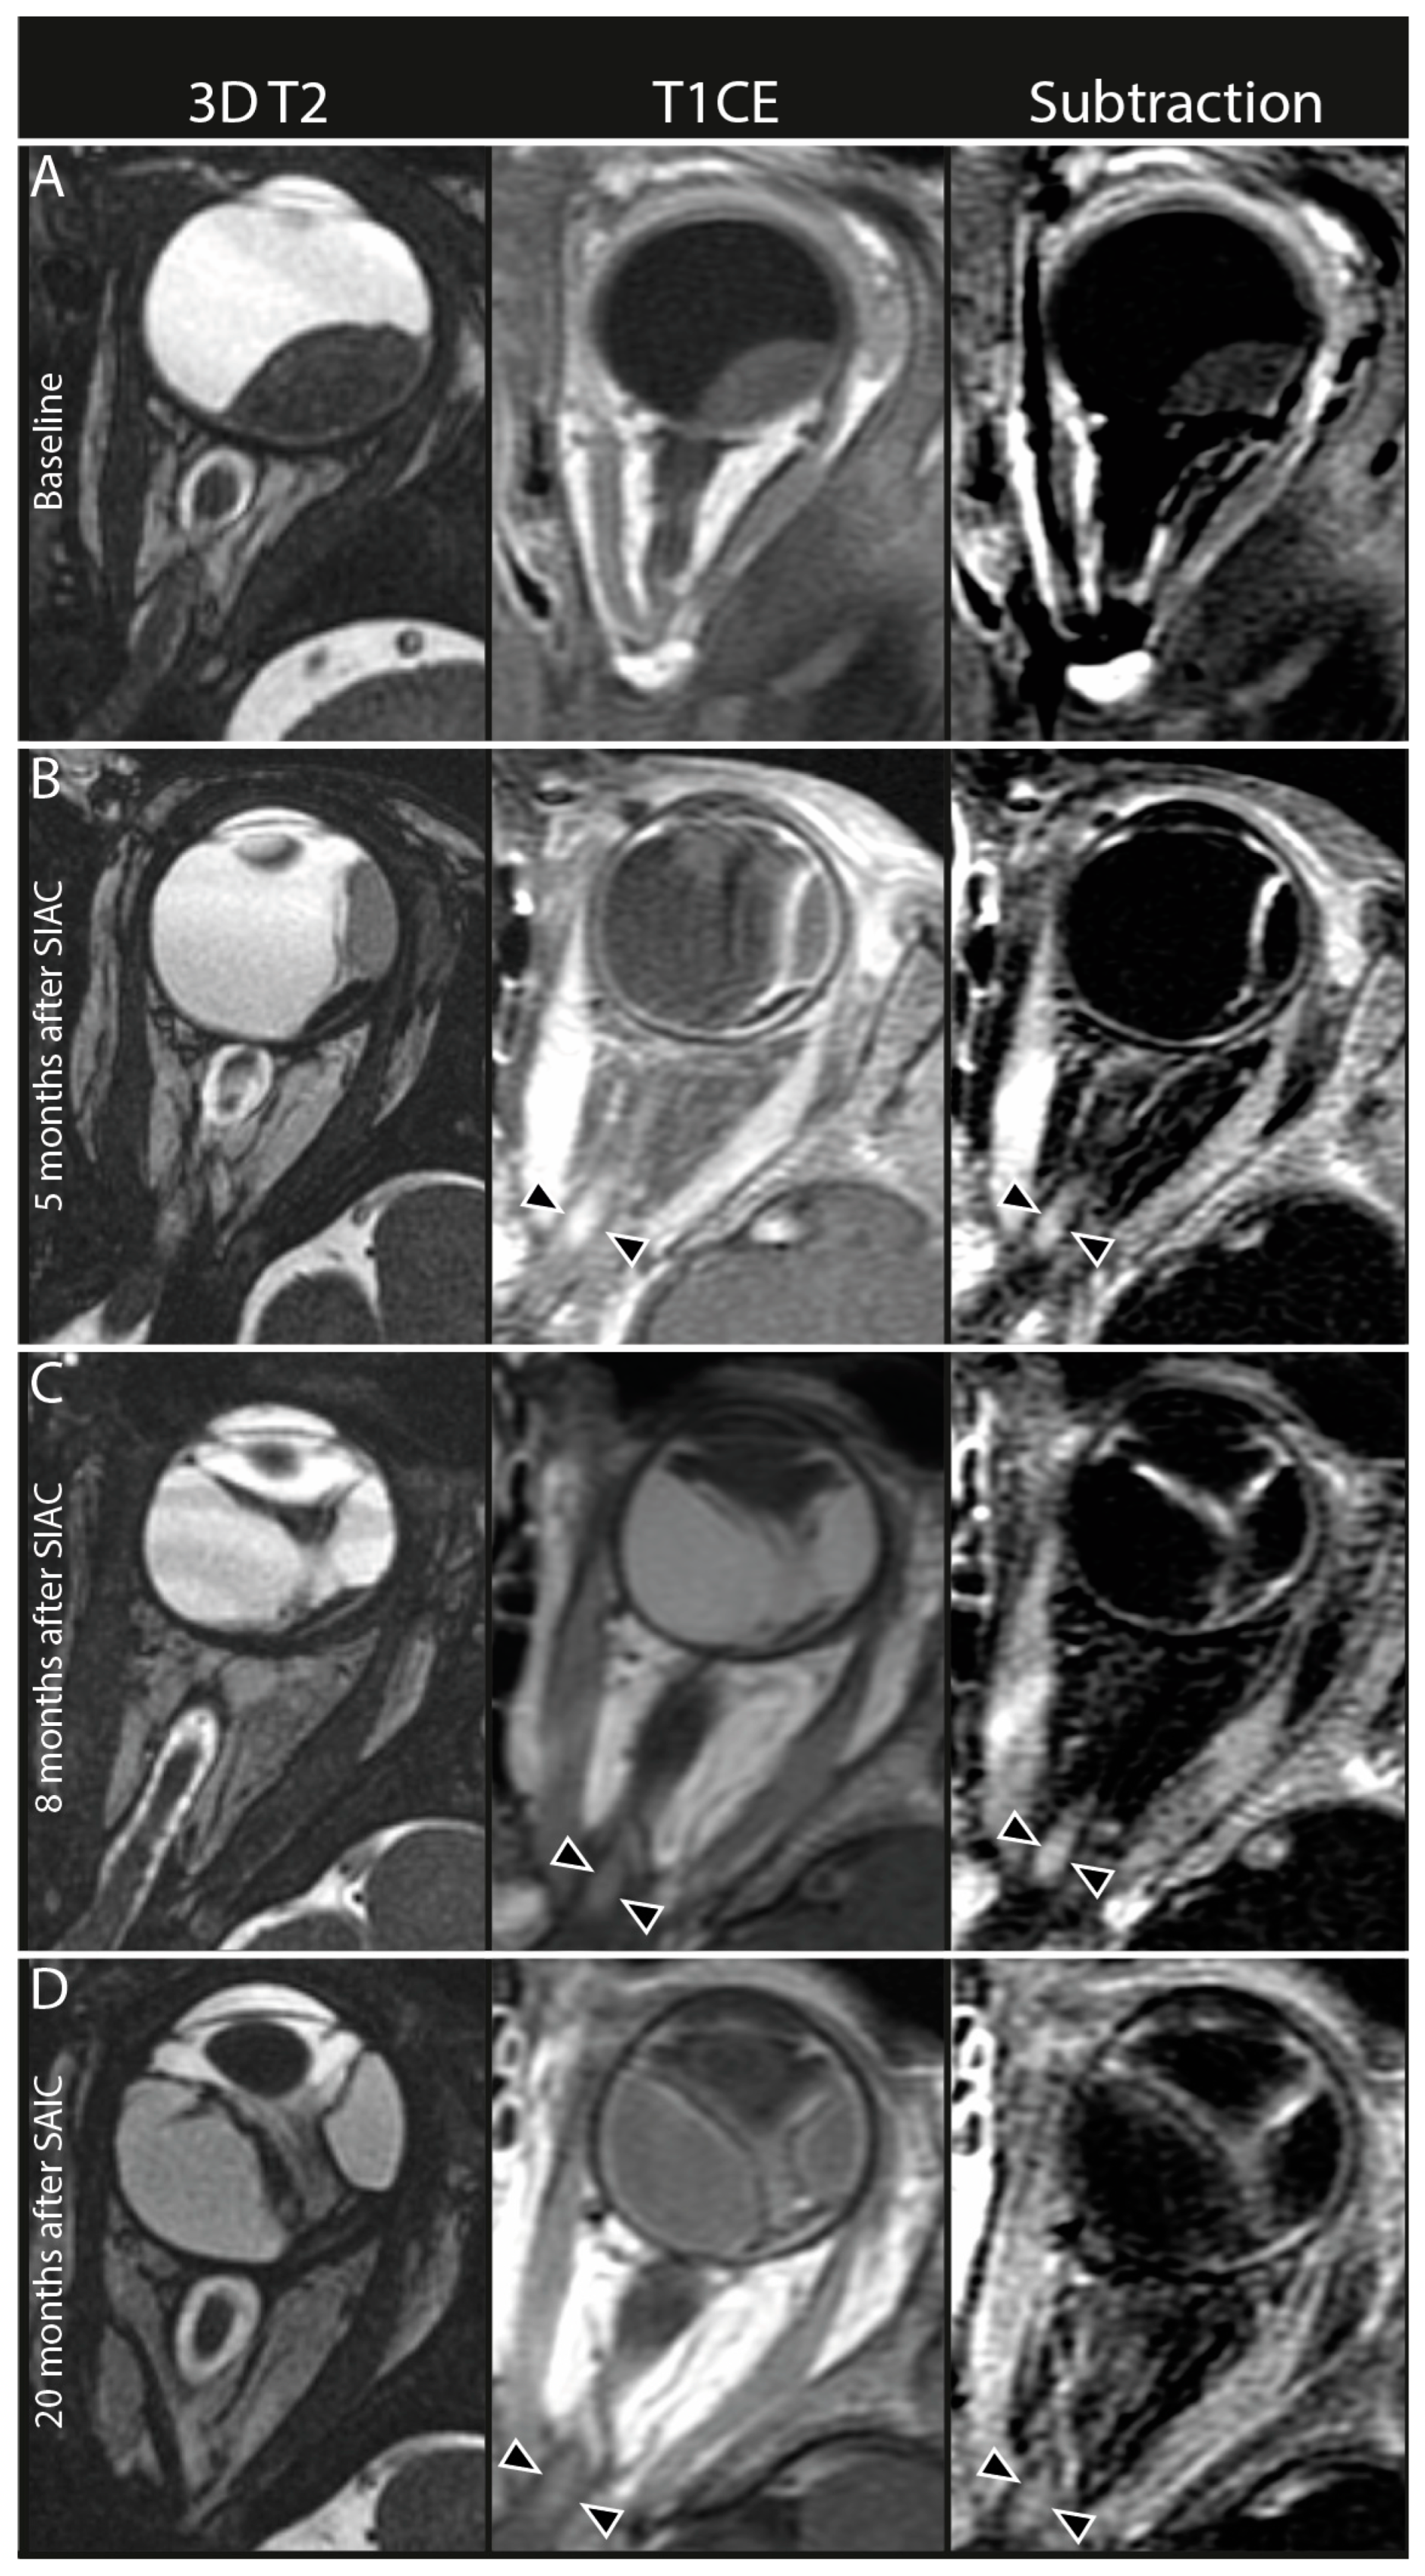

3.2. Qualitative Imaging Features

| Enhancement of the anterior eye segment | n/a | 55/231, 24 (18–30) |

| Choroidal infarction | n/a | 24/233, 10 (7–15) |

| Choroidal thickening | n/a | 62/234, 27 (21–33) |